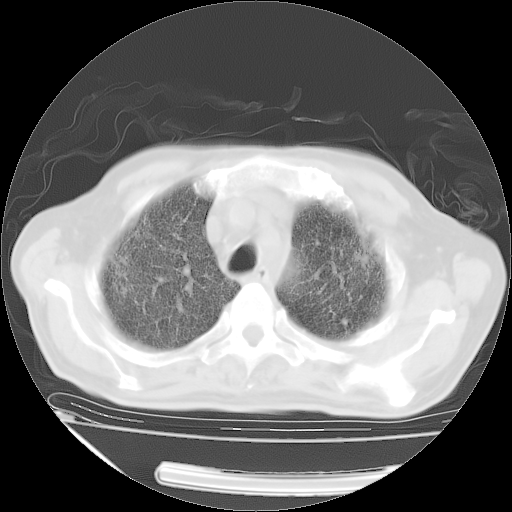

仔细阅读病史资料和CT,我觉得两肺粟粒结核要高度怀疑。

昨天我们影像科主任说由于12天前在齐鲁医院的肺部CT无确切改变,所以不考虑肺结核。

但我们感染病科老主任认为粟粒性肺结核可能性大。

今天带四次肺CT片到市医院,影像科4~5个主任都认为不考虑粟粒性肺结核。主要理由是在3月19日、4月2日、4月27日的CT片没有见到确切异常(肺结核)影像。影像科主任们建议找呼吸内科主任,呼吸内科主任认为首先考虑粟粒性肺结核。

甲强龙80mg/日+抗结核治疗(异烟肼+利福霉素+乙胺丁醇)10天。复查肺部CT。

治疗10天肺部CT